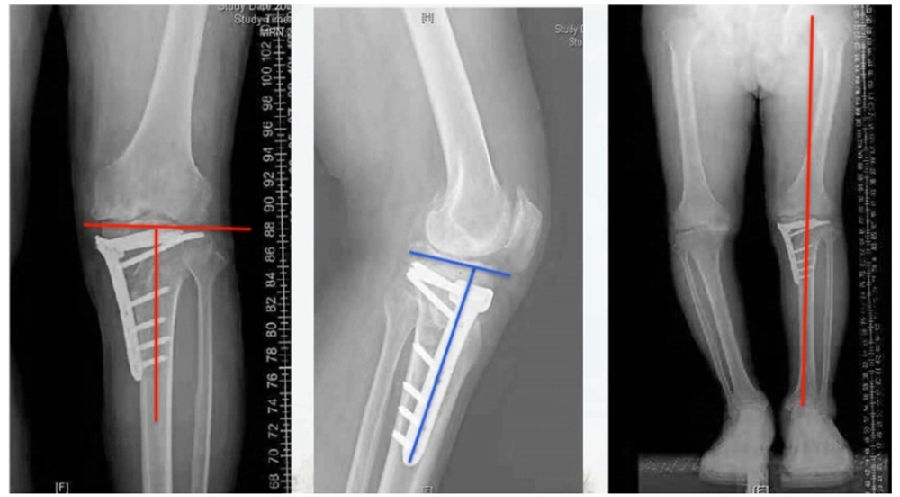

典型病例,男性,65岁,农民,双膝内翻16度。

术前影像

第一次为该患者做了传统上行开放截骨,撑开角度较大,术后用三种方法测量髌骨高度,发现髌骨高度受到影响,髌骨变低了。

左膝上行OWHTO(初次)

上行OWHTO髌骨高度测量

ISI法测量髌骨无明显变化;CDI、BPI法测量髌骨降低明显;患者屈膝锻炼困难。

第二次来院做另一侧肢体时,采用下行截骨,术后患者髌骨高度,无论用哪种方法测量都无明显变化,而且患者膝关节功能迅速得到恢复。

右膝下行OWHTO(再次)

下行OWHTO髌骨高度测量

ISI法测量髌骨无明显变化;CDI、BPI法测量髌骨无明显变化;患者屈膝明显改善。